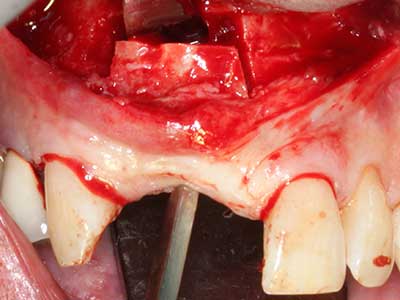

Bei der Knochenblockentnahme zeigen sich weitere Vorteile für die Piezochirurgie: Neben der bereits beschriebenen hohen Präzision bei der Osteotomie stellt sich gerade die Verwendung der dünnen Sägespitzen als besonders materialschonend heraus. Bei der Verwendung insbesondere von Lindemannfräsen sind mit deutlich höheren Entnahmeverlusten durch die dickere Instrumentenspitze zu rechnen (Lakshmiganthan, Gokulanathan et al. 2012). Die insbesondere bei retromolar entnommenen Blocktransplantaten notwendige basale Abtrennung wird durch speziell hierfür vorgesehene rechtwinklige Sägen erleichtert, so dass die Piezochirurgie als präzises, übersichtliches und sicheres Verfahren zur retromolaren Knochenblockgewinnung angesehen wird (Happe 2007) (Abb. 1-12).

Knochengewebe ist nicht nur rein mineralisch, sondern auch in wesentlichen Anteilen aus Kollagenfasern aufgebaut. Dies gewährleistet neben einer guten Druckfestigkeit eine gewisse Flexibilität, welche für die Durchführung von Augmentationen genutzt werden kann. Bei der klassischen Expansionsplastik im Sinne eines Bone Splittings wird der atrophierte Kieferkamm in seiner Längsachse gespalten und nach Erreichen einer ausreichenden Osteotomietiefe vorsichtig aufgedehnt (Abb. 13-16), idealerweise ohne den Kiefer wesentlich zu deperiostieren (Brugnami, Caiazzo et al. 2014, Stricker, Fleiner et al. 2014). Bewährt haben sich Schrauben- und Plattensysteme mit zunehmender Expansionsdistanz, um die beiden Knochenlamellen unterhalb der Bruchschwelle voneinander zu distanzieren. In der Regel werden Restknochenbreiten von mindestens 3-4 mm gefordert (Chiapasco, Zaniboni et al. 2006), um eine ausreichende Flexibilität und knöcherne Bedeckung der einzubringenden Implantate zu gewährleisten. Ggf. kann eine ein- oder beidseitige vertikale Entlastungsosteotomie die Flexibilität verbessern. Als Alternative zur klassischen Technik wurde eine Kombination mit weiteren augmentativen Techniken vor allem auf der bukkalen Seite beschrieben.

Mittels Piezosägen erfolgt die Anlage des Splittings besonders schonend und ohne wesentliche Dimensionsverluste, so dass sich keine signifikanten Unterschiede von Implantaten im gesplitteten Kiefer im Vergleich zum nicht defizitären Alveolarkamm gezeigt haben (Chiapasco, Zaniboni et al. 2006, Danza, Guidi et al. 2009). Gerade beim lokal begrenzten und tiefen Splitting ist jedoch stets auf eine ausreichende Wasserkühlung zu achten, um thermische Belastungen in den apikalen Osteotomiebereichen zu vermeiden.